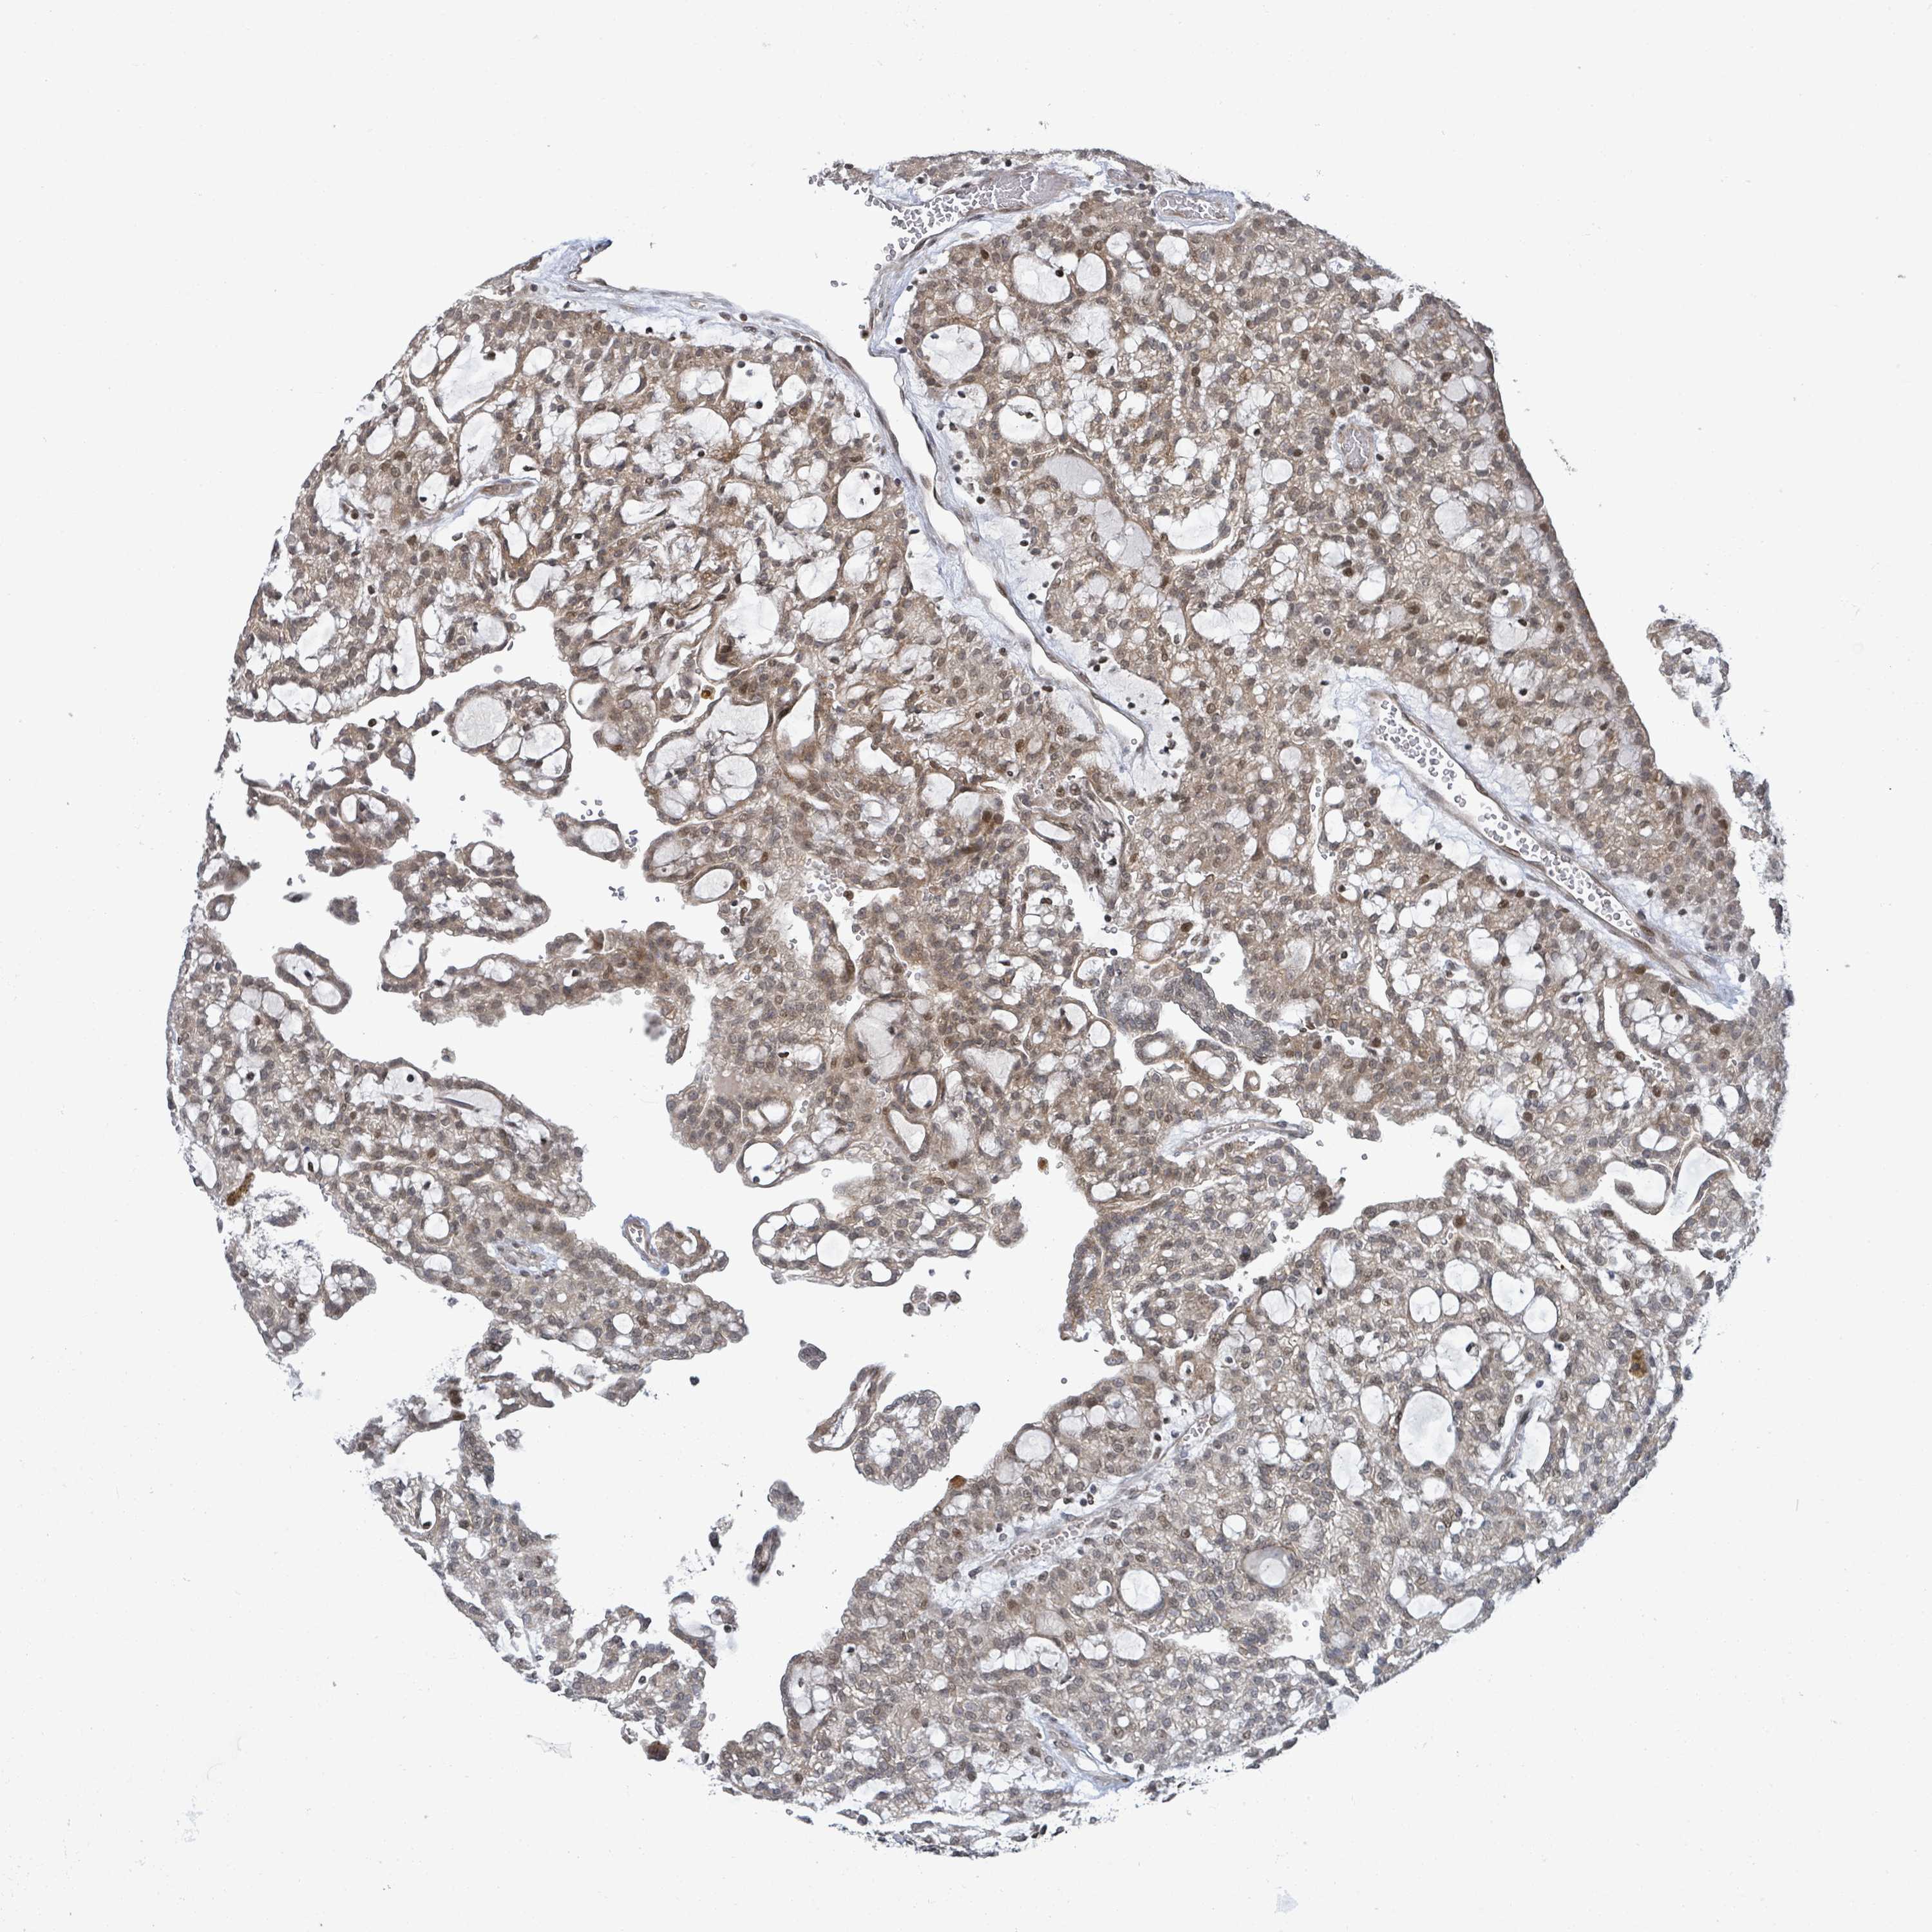

KIDNEY RENAL CLEAR CELL CARCINOMA (VALIDATION) - Interactive survival scatter ploti

The Survival Scatter plot shows the clinical status (i.e. dead or alive) for all individuals in the patient cohort, based on the same data that underlies the corresponding Kaplan-Meier plots. Patients that are alive at last time for follow-up are shown in blue and patients who have died during the study are shown in red.

The x-axis shows the expression levels (FPKM) of the investigated gene in the tumor tissue at the time of diagnosis. The y-axis shows the follow-up time after diagnosis (years). Both axes are complimented with kernel density curves demonstrating the data density over the axes. The top density plot shows the expression levels (FPKM) distribution among dead (red) and alive patients (blue). The right density plot shows the data density of the survived years of dead patients with high and low expression levels respectively, stratified using the cutoff indicated by the vertical dashed line through the Survival Scatter plot. This cutoff is automatically defined based on the FPKM cutoff that minimizes the p-score. The cutoff can be changed by dragging the vertical line or by entering a cutoff value in the square labeled "Current cut-off".

Under the Survival Scatter plot the p-score landscape (black curve; left axis) is shown together with dead median separation (red curve; right axis). Dead median separation is the difference in median mRNA expression between patients who have died with high and low expression, respectively. It is calculated as follows: median FPKM expression of dead patients with high expression - median FPKM expression of dead patients with low expression. This is intended to aid the user in visually exploring custom cutoffs and the associated p-scores and dead median separation.

Individual patient data is displayed and can be filtered by clicking on one or more of the category buttons on the top of the page. Categories describing expression level and patient information include: high, low, alive, dead, female, male and tumor stages. The scale of the x-axis can be toggled between linear and log-scale by clicking on the "x log" button. Mouse-over function shows TCGA ID, patient information and mRNA expression (FPKM) for each patient.

& Survival analysisi

Kaplan-Meier plots summarize results from analysis of correlation between mRNA expression level and patient survival. Patients were divided based on level of expression into one of the two groups "low" (under cut off) or "high" (over cut off). X-axis shows time for survival (years) and y-axis shows the probability of survival, where 1.0 corresponds to 100 percent.

SBF2 is not prognostic in Kidney Renal Clear Cell Carcinoma (validation)

Best expression cut offi

Based on the FPKM value of each gene, patients were classified into two groups and association between prognosis (survival) and gene expression (FPKM) was examined. The best expression cut-off refers the FPKM value that yields maximal difference with regard to survival between the two groups at the lowest log-rank P-value. Best expression cut-off was selected based on survival analysis .

When clicking on this number, the vertical dashed line indicating cut-off, the interactive survival plot, and the Kaplan-Meier curve will be adjusted to show results based on the best expression cut-off.

: 14.18

P scorei

Log-rank P value for Kaplan-Meier plot showing results from analysis of correlation between mRNA expression level and patient survival.

N/A

TCGA RNA samplesi

RNA-seq data is reported as average FPKM (number Fragments Per Kilobase of exon per Million reads), generated by the The Cancer Genome Atlas (TCGA) .

Normal distribution across the dataset is visualized with box plots, shown as median and 25th and 75th percentiles. Points are displayed as outliers if they are above or below 1.5 times the interquartile range. FPKM values of the individual samples are presented next to the box plot.

Average pTPM 16.2

Number of samples 100